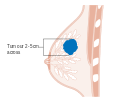

- Stage. Breast cancer staging using the TNM system is based on the size of the tumor (T), whether or not the tumor has spread to the lymph nodes (N) in the armpits, and whether the tumor has metastasized (M) (i.e. spread to a more distant part of the body). Larger size, nodal spread, and metastasis have a larger stage number and a worse prognosis.

The main stages are:- Stage 0 is a pre-cancerous or marker condition, either ductal carcinoma in situ (DCIS) or lobular carcinoma in situ (LCIS).

- Stages 1–3 are within the breast or regional lymph nodes.

- Stage 4 is 'metastatic' cancer that has a less favorable prognosis since it has spread beyond the breast and regional lymph nodes.

Stage T2 breast cancer

-